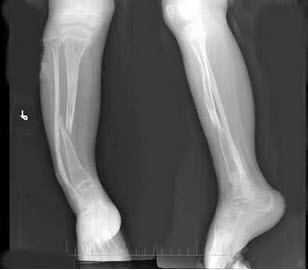

83、单项选择题

男,14岁,偶然发现双膝部肿块1天,双膝关节摄片如图,最可能的诊断是()

A.骨瘤

B.骨软骨瘤

C.局限性骨皮质增厚

D.软骨肉瘤

E.以上均不正确